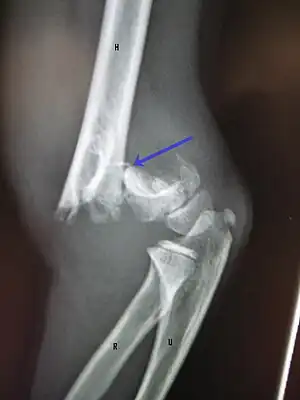

Diagnosis

A supracondylar humerus facture is diagnosed by x-ray and the injured limb will be examined to assess the surrounding soft tissue, neurovascular status, and to identify any other injuries to the affected area.[5] Pain, swelling, and deformity near the elbow or arm area is common and a bleed near the fracture may result in an effusion in the elbow joint. With severe displacement, there may be an anterior dimple from the proximal bone end trapped within the biceps muscle. The skin is usually intact. If there is a laceration that communicates with the fracture site, it is an open fracture, which increases infection risk. For fractures with significant displacement, the bone end can be trapped within the biceps muscle with resulting tension producing an indentation to the skin, which is called a "pucker sign".

X-rays

Diagnosis is confirmed by x-ray imaging. Antero-posterior (AP) and lateral view of the elbow joint should be obtained. Any other sites of pain, deformity, or tenderness should warrant an X-ray for that area too. X-ray of the forearm (AP and lateral) should also be obtained for because of the common association of supracondylar fractures with the fractures of the forearm. Ideally, splintage should be used to immobilise the elbow at 20 to 30 degrees flexion in order to prevent further injury of the blood vessels and nerves while doing X-rays. Splinting of fracture site with full flexion or extension of the elbow is not recommended as it can stretch the blood vessels and nerves over the bone fragments or can cause impingement of these structures into the fracture site.[3]